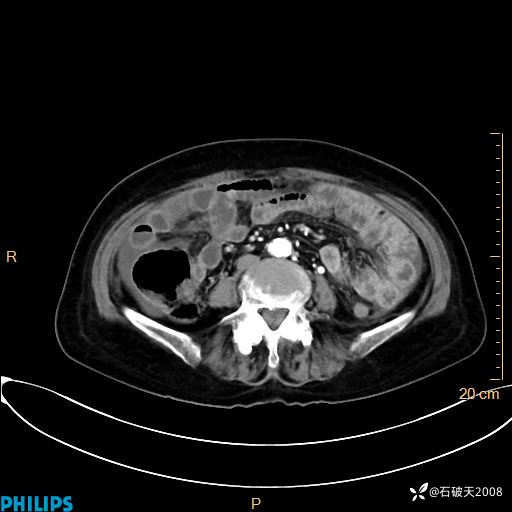

静脉期